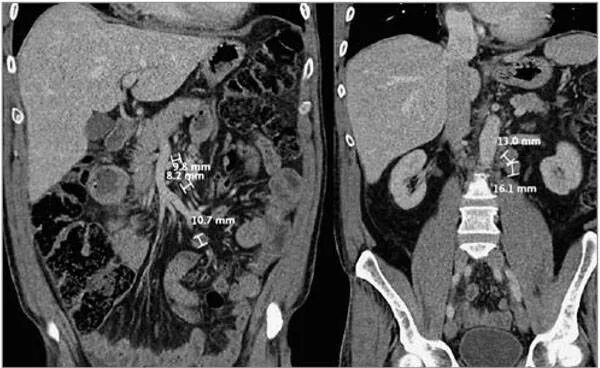

Рак брюшных лимфоузлов